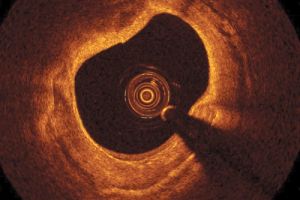

LightLab, originally co-founded by OCT pioneer Jim Fujimoto, applied OCT to the challenging task of catheter-based imaging inside cardiovascular systems as an aid to diagnosis and surgical treatment. Schmitt will discuss the hurdles involved and the particular story of LightLab Imaging at next month's Strategies in Biophotonics conference in Boston.

In LightLab's case, some of the application-specific hurdles involved in intravenous OCT included the difficulties of imaging in blood, which necessitated innovations in delivery devices and electro-optics; and proving the clinical utility in current coronary interventions, while convincing cardiologists to consider the potential benefits of more advanced imaging techniques.

The company's work on OCT in cardiovascular systems includes the Ilumien Optis platform, combining OCT with a measurement of artery obstruction via a parameter called fractional flow reserve. Ilumien Optis is designed to assist surgeons during coronary interventions and the placement of stents, and received FDA clearance for use in the US in October 2013.